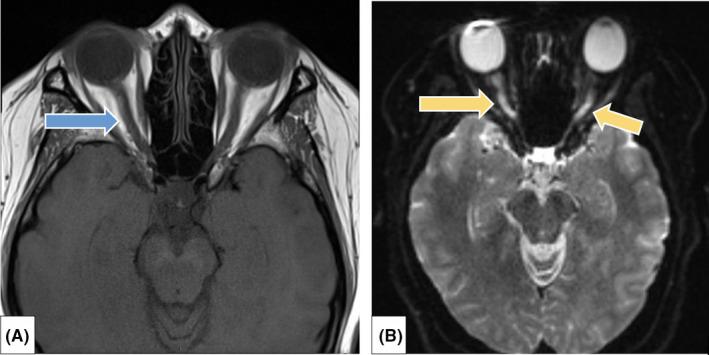

The diagnostic dilemma of bilateral optic neuritis and idiopathic intracranial hypertension coexistence in a patient with recent COVID-19 infection.

Owing to autoantibody production and thrombophilic disorders in COVID-19, physicians must have low threshold to investigate secondary IIH and demyelinating disorders in patients with headache and decreased vision following recent COVID-19 infection.